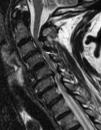

Las técnicas de imagen proporcionan una imagen anatómica excelente de la columna cervical. La elección de cada una de ellas dependerá del escenario clínico y de las alternativas terapéuticas. La radiografía simple sigue siendo fundamental, ya que permite valorar la alineación, las alteraciones óseas y el seguimiento tras el tratamiento. La mayor resolución de contraste de la resonancia magnética permite la valoración de las partes blandas, incluyendo los discos intervertebrales, los ligamentos, la médula ósea y la médula espinal. El papel de la tomografía computarizada en el estudio de la patología degenerativa ha cambiado en los últimos tiempos debido a la gran resolución espacial y su capacidad para visualizar el componente óseo.

Imaging techniques provide excellent anatomical images of the cervical spine. The choice to use one technique or another will depend on the clinical scenario and on the treatment options. Plain-film X-rays continue to be fundamental, because they make it possible to evaluate the alignment and bone changes; they are also useful for follow-up after treatment. The better contrast resolution provided by magnetic resonance imaging makes it possible to evaluate the soft tissues, including the intervertebral discs, ligaments, bone marrow, and spinal cord. The role of computed tomography in the study of degenerative disease has changed in recent years owing to its great spatial resolution and its capacity to depict osseous components.